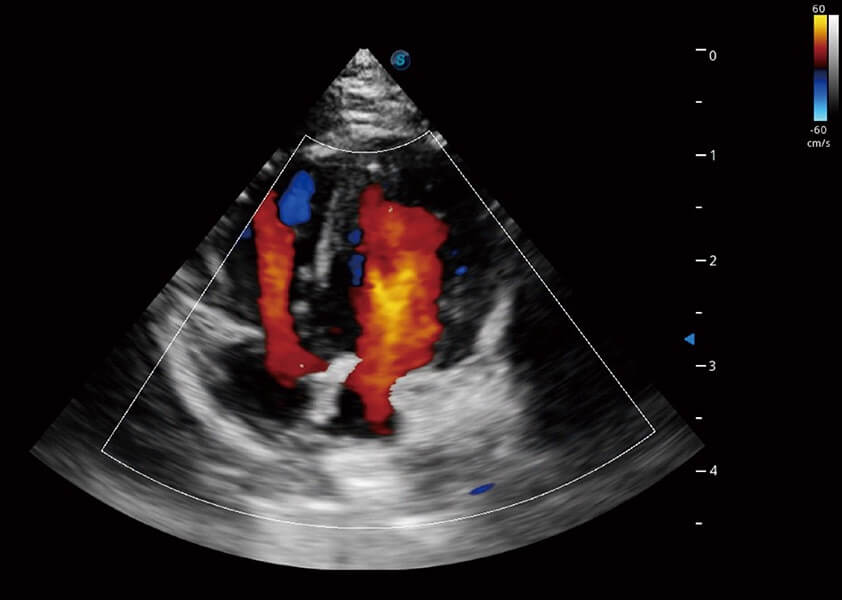

ProPet 60 作为一款高端台式动物超声设备,为动物医生的日常诊断提供了一系列贴合动物临床需求、解决临床实际问题的高级成像功能。凭借全系列高清探头,满足医生对腹部、心脏、生殖、浅表、肌骨等成像的所有需求,切实帮助您提升检查效率,提高诊断信心。

动物是人类最亲密的朋友和最值得信赖的伙伴。竞技宝(JJB)官方网站也一直致力于探索动物专用的超声影像解决方案。 全新推出的ProPet系列,是竞技宝(JJB)官方网站在动物超声影像智能化、专业化、精准化的一次跨越式革新。动物不能用言语来表述自己的不适,通过超声影像,ProPet系列搭建了动物医生与不同物种沟通的“桥梁”,为动物医生注入了“治愈之力”。